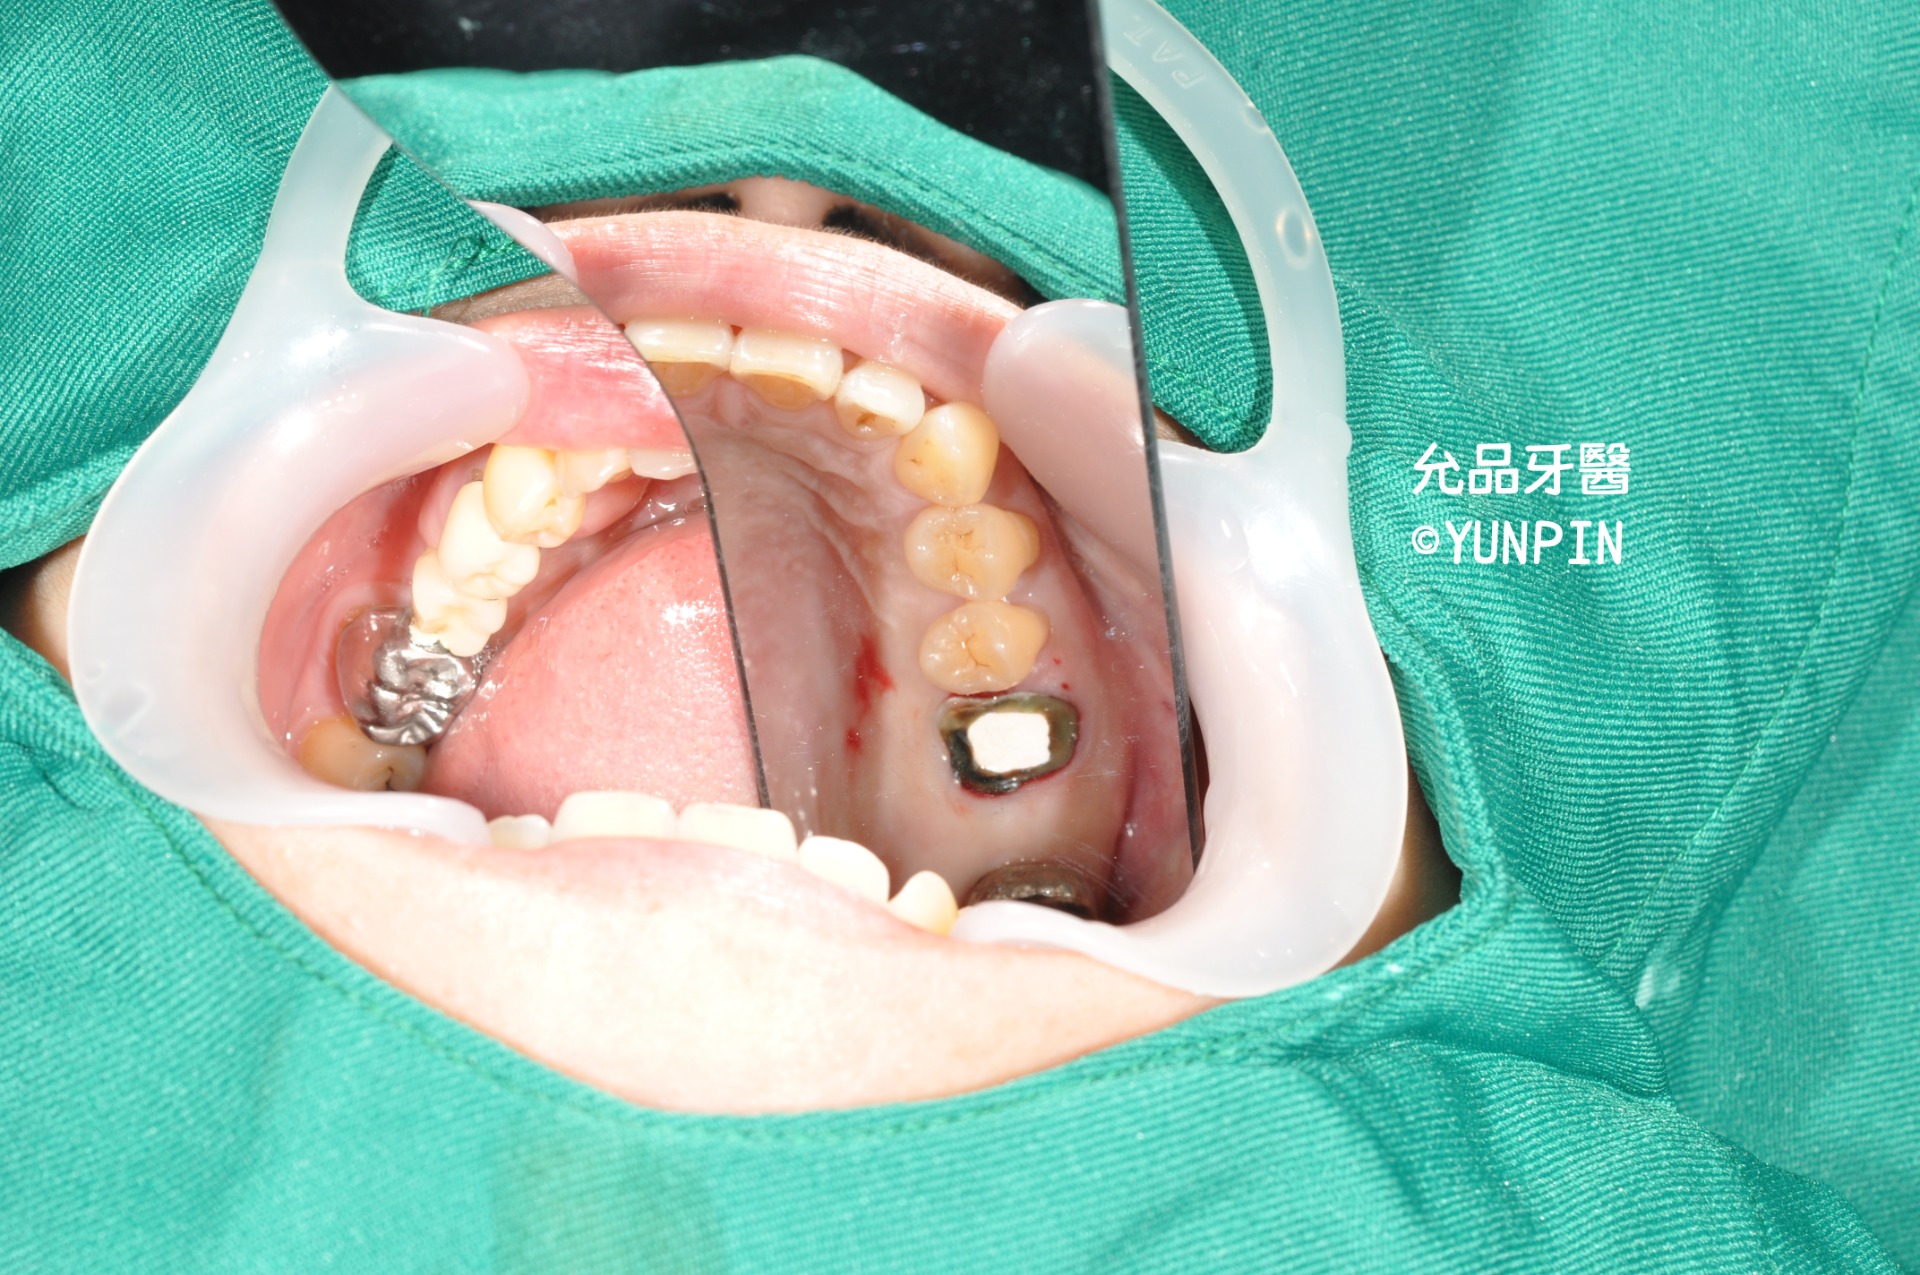

手術前

患者牙套下2次蛀牙,拆除牙套後二次蛀牙已至牙根,

討論過後,進行拔除並施作齒槽骨脊保存手術。